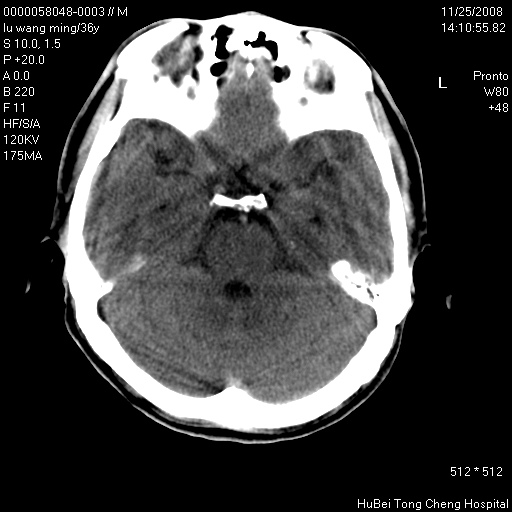

患者 男,36岁。头部烧伤36年伴溃烂,经久不愈。患者几个月大时,倒入火炉不幸烧伤头部,后长期溃烂,经久不愈。

临床诊断:1)头皮烧伤并感染。2)颅骨病损?

颅脑ct轴位平扫(层厚、层距均匀10mm),图像如下:

以骨质破坏为为,边缘呈虫噬样改变,多砂粒样钙钙化或死骨,伴软组织及硬膜外积脓,考虑为结核感染可能性大,建议细菌培养。

额顶局部骨质破坏缺损

患者有明确的病史,且经久不愈,更该考虑软组织化脓性感染,颅骨损害伴硬膜下下积脓

结合病史考虑颅骨慢性骨髓炎

结合病史考虑颅骨慢性骨髓炎伴硬膜外积脓。

骨质破坏,边缘呈虫噬样改变,结合患者明确烧伤史,经久不愈,考虑软组织化脓性感染,颅骨损害伴硬膜下积脓。